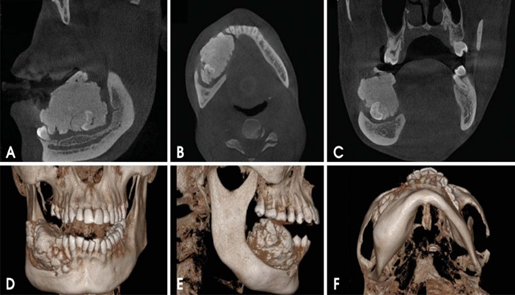

| - Phát hiện bệnh lý xương hàm: CBCT giúp các BS phẫu thuật hàm mặt phát hiện, chẩn đoán, đánh giá độ lan rộng của các bệnh lý xương hàm xâm lấn như u nguyên bào men, nang sừng do răng, ung thư xương hàm, ….. từ đó lên kế hoạch điều trị cũng như vị trí mổ phù hợp | | |

| - CBCT trong việc lập kế hoạch điều trị Implant sử dụng hình ảnh 3D và đa lớp cắt để xác định chính xác chiều cao, độ rộng và giải phẫu của phần xương hàm và xương ổ răng cũng như mối tương quan vùng mất răng với cấu trúc giải phẫu liền kề như ống thần kinh răng dưới. Đặt Implant với máng hướng dẫn phẫu thuật có thể được thực hiện với các dữ liệu CBCT. Với khả năng 3 chiều của CBCT, các nhà lâm sàng có thể quyết định liệu có cần đến việc ghép xương, nâng xoang trước khi đặt Implant hay không cũng như chọn kích thước implant phù hợp nhất cho từng vùng xương. | | |